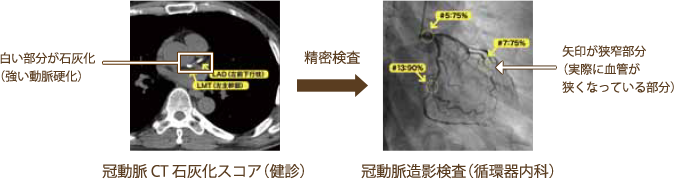

⑤冠動脈CT石灰化スコア

心臓CTで3本の冠動脈の石灰化を調べることで、冠動脈硬化の程度や動脈硬化が進んだ状態を示すプラーク(血管壁の一部が限定的に盛り上がっている状態)が広がっているかなどが分かります。冠動脈プラークの存在は、狭心症や心筋梗塞発症の基盤になります。検査に造影剤は使用しませんので、どなたでもご利用いただけます。